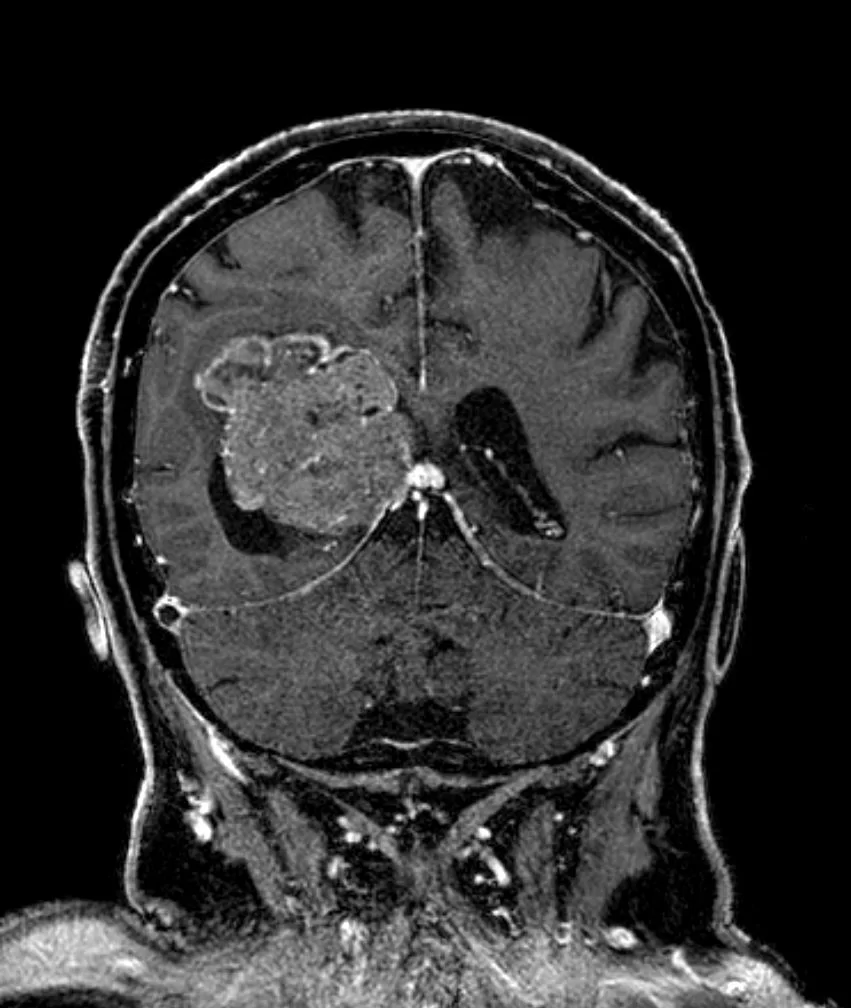

Η μαγνητική τομογραφία ανέδειξε ευμεγέθη χωροκατακτητική εξεργασία εντός της δεξιάς πλάγιας κοιλίας του εγκεφάλου.